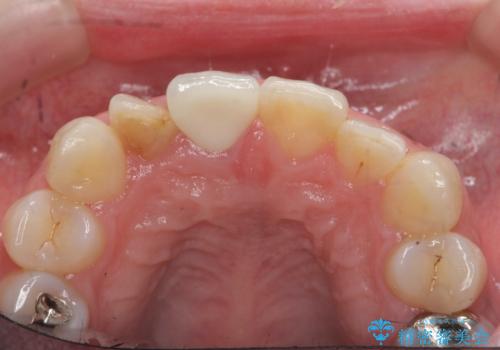

前歯の変色 セラミッククラウンによる審美性の回復

根尖に病変は見られず、根管治療は行わずに仮歯・ジルコニアクラウンを作製、装着することで審美性を回復しました。

- 12.1万円 (仮歯・ジルコニアクラウン)費用は治療当時の料金となります

神経の治療を行った歯は、徐々に変色し審美障害をきたすことはから当院ではセラミッククラウンの装着をお勧めしております。